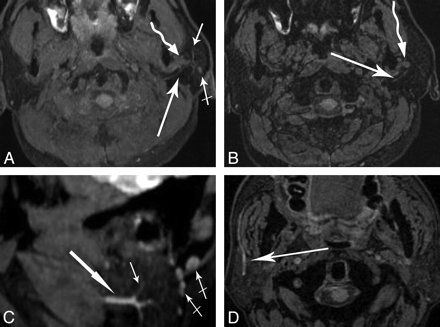

Oblique-sagittal and coronal reconstructed images demonstrated the main trunks and cervicofacial divisions (Fig 3). Curved reconstructed images could display the bifurcation of the temporofacial and cervicofacial divisions with the parotid ducts in 1 image (Fig 4 A, -B). Oblique axial reconstructed images showed the main trunk and initial part of the temporofacial nerve (Fig 5 A); sagittal reconstructed images showed the parotid duct (Fig 5C). The reconstructed images presented more information than the source images (Fig 5B, -D).

Oblique-sagittal coronal MPR (A and B) and MIP (C and D) images of the intraparotid facial nerve demonstrate its cervicofacial division (long arrows) and small branches (short arrows). The cervicofacial division separates the deep and superficial lobes of the parotid gland.

A and B, Axial MIP image (A) and source image (B) show the facial nerve (long arrow) and retromandibular vein (curved arrow). In the MIP image, more information concerning the branches of the parotid duct (short arrow) and lymph node (crossed arrow) is demonstrated, and the length of the facial nerve is shown to be longer than that in the source image. C and D, Sagittal MIP image (C) and axial source image (D) show that the parotid duct (long arrows) is in the anterior and inferior portion of the gland. In the sagittal MIP image, the branches of the parotid duct (short arrow) and lymph nodes (crossed arrow) are shown.